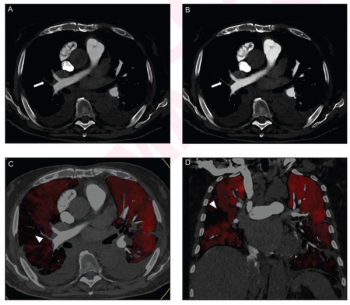

Performing computed tomography pulmonary angiography (CTPA) with a high-pitch photon counting detector (PCD) offers enhanced signal-to-noise ratio (SNR) and contrast-to-noise ratio (CNR) at a reduced radiation dose in comparison to employing an energy-integrating detector (EID), according to new research.